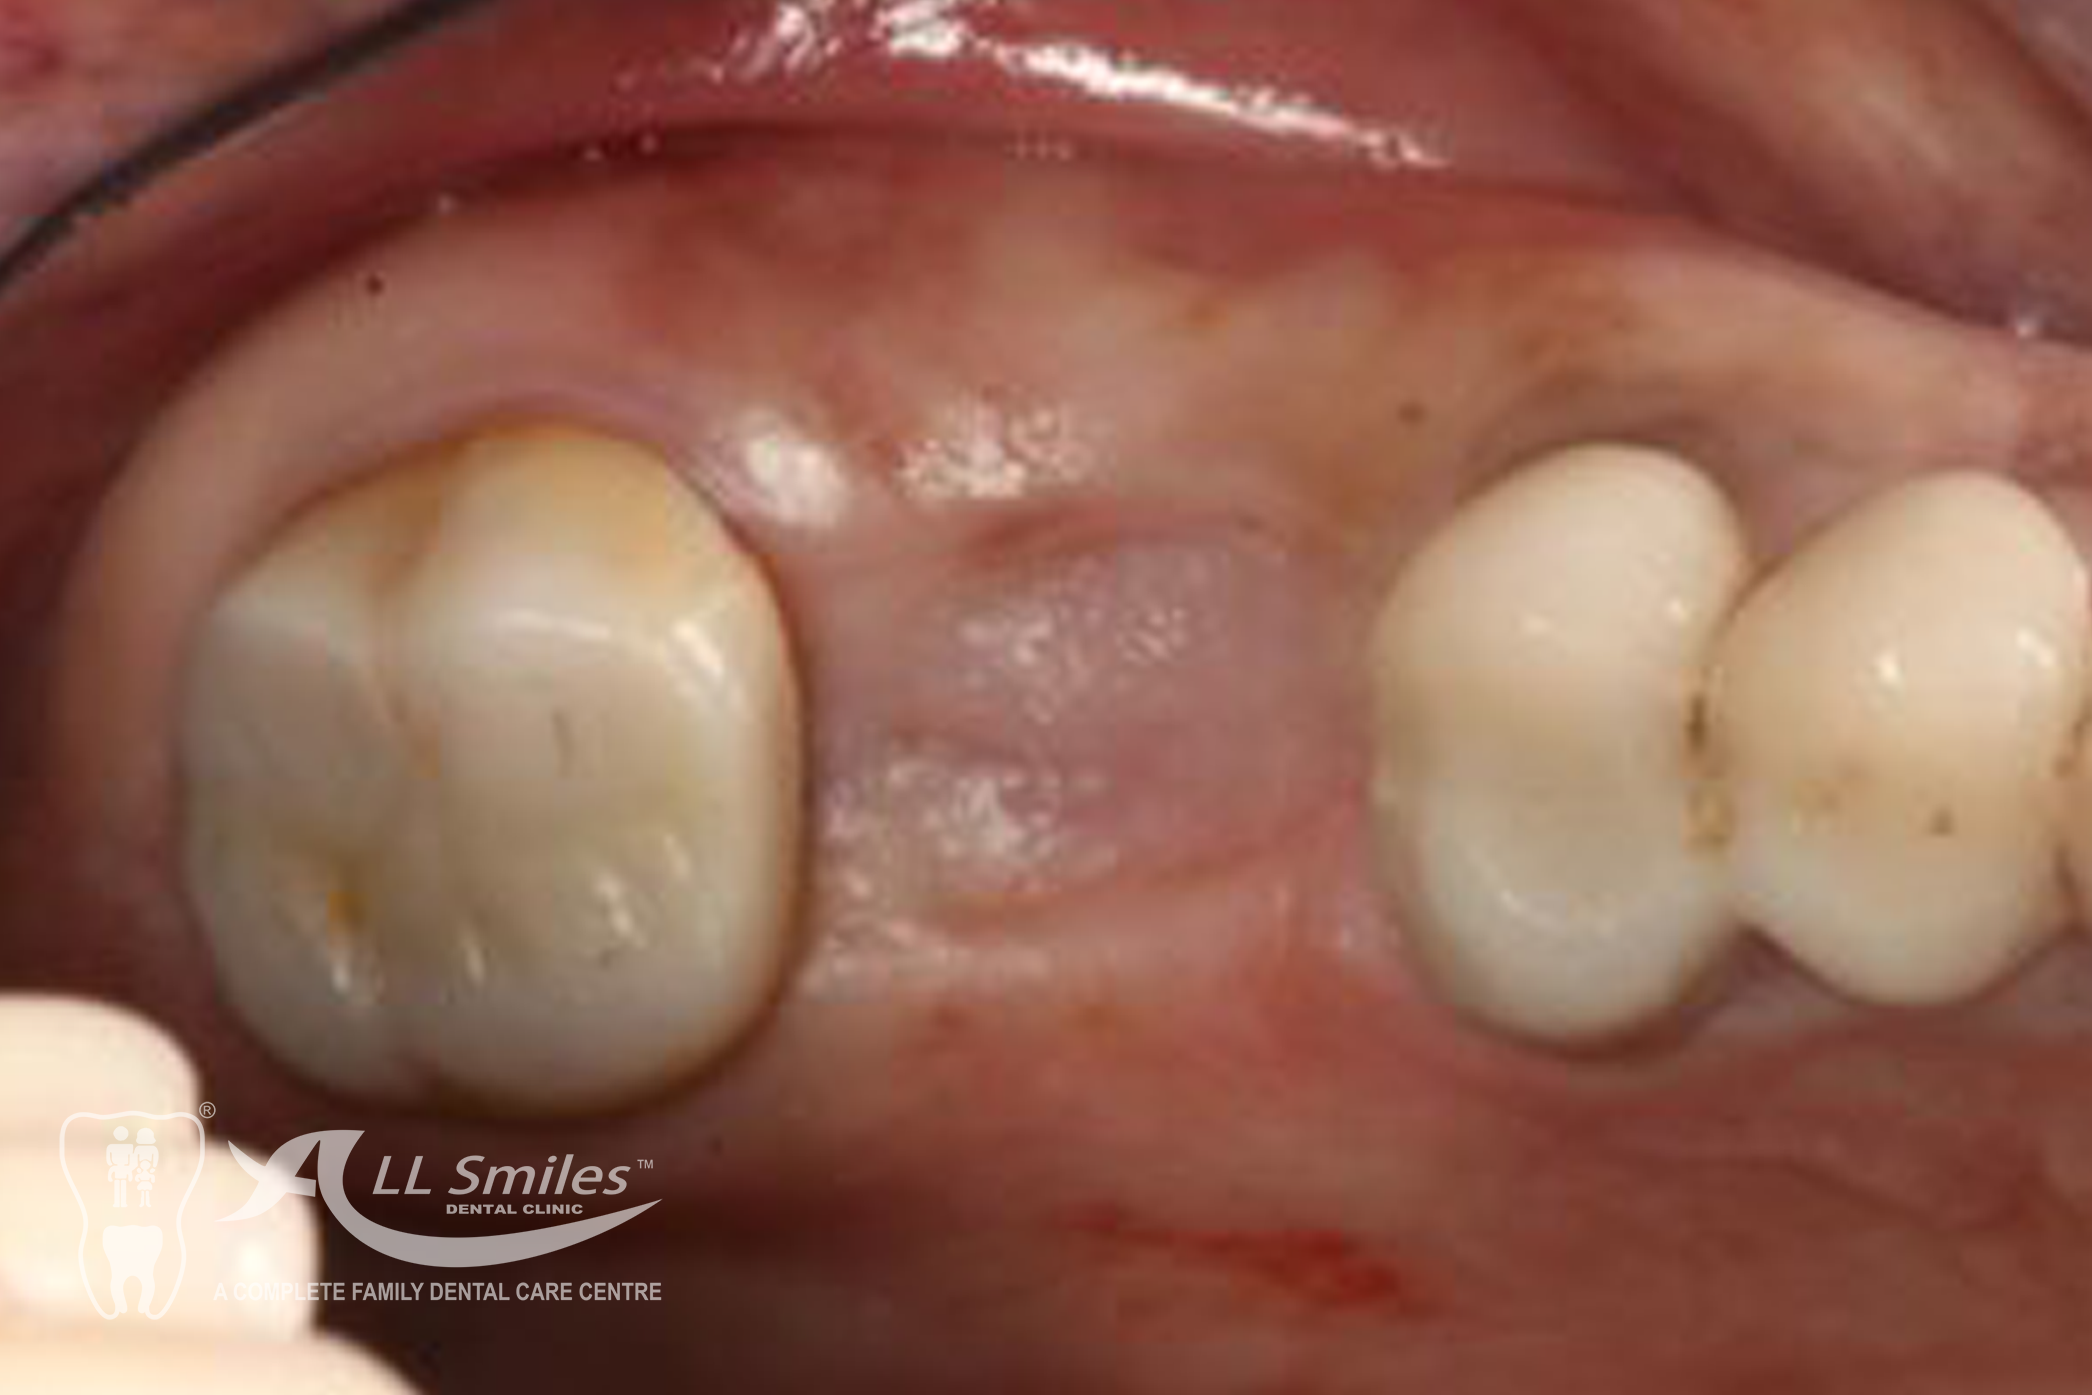

Dental Implants Gallery